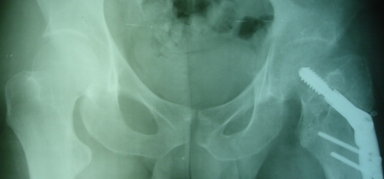

Уважаемые коллеги, приношу извинения за перерыв в работе -

был в командировке. За это время больному сделали КТ и,  сегодня,

снимки. Укорочение конечности - 1-1,5 см, ШДУ-115 градусов, замедленная консолидация,

остеопороз.

Вопрос о тактике дальнейшего ведения пациента (напоминаю, возраст 19

лет)?